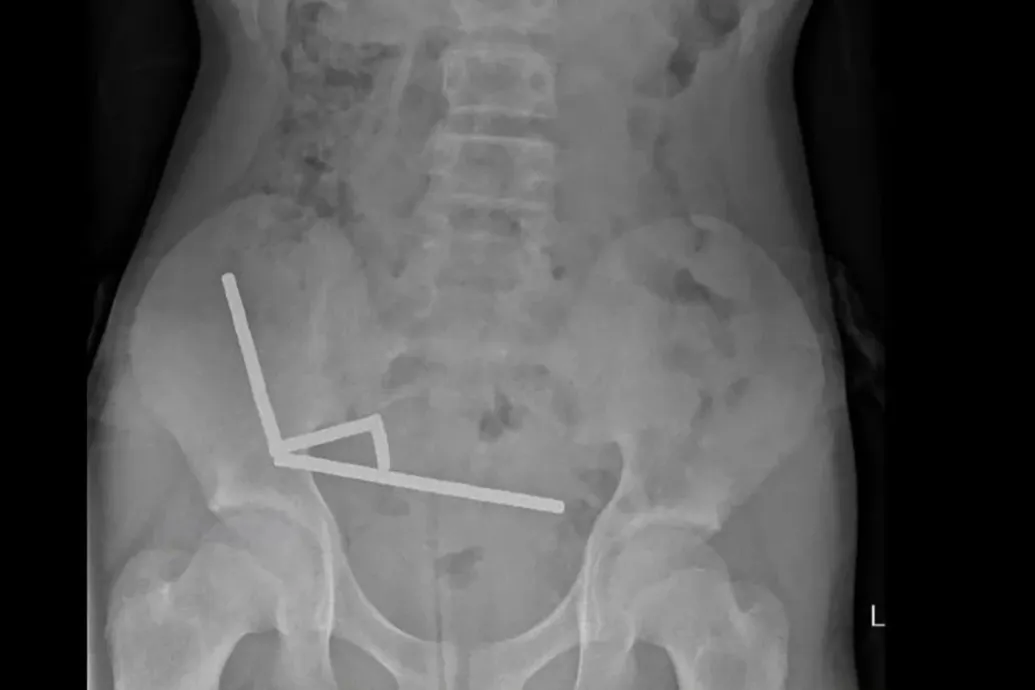

Száz darab erős mágnest rendelt a Temuról, hogy lenyelhesse őket, meg kellett műteni a 13 éves új-zélandi fiút

A mágnesek egymáshoz tapadtak odabenn, négy napig bírta a hasi görcsöket a fiatal.